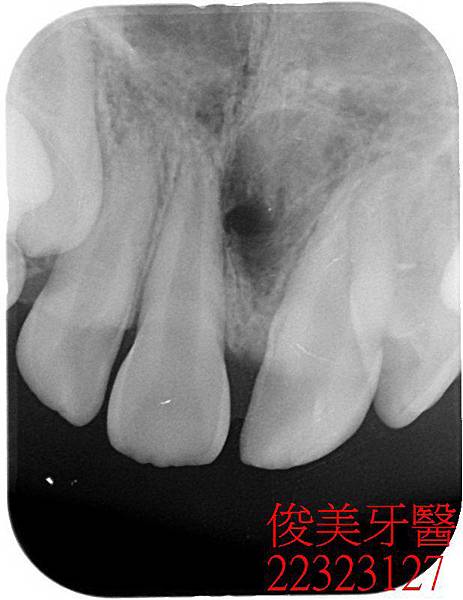

患者的上顎犬齒也一直長不出來。

治療中.....患者的犬齒雖已有空間,仍無法萌出...

採雷射處理....無傷口

裝上矯正器導引牙齒生長到正常位置....